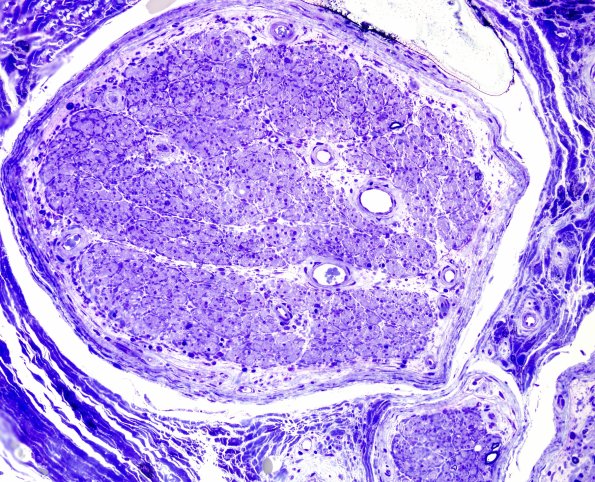

Plastic sections confirm the marked variability of axon density. (plastic sections) ---- Not shown: The CD3 immunostain highlights a population of T lymphocytes; in contrast, CD20 immunoreactivity shows only rare B lymphocytes within the inflammatory infiltrates.